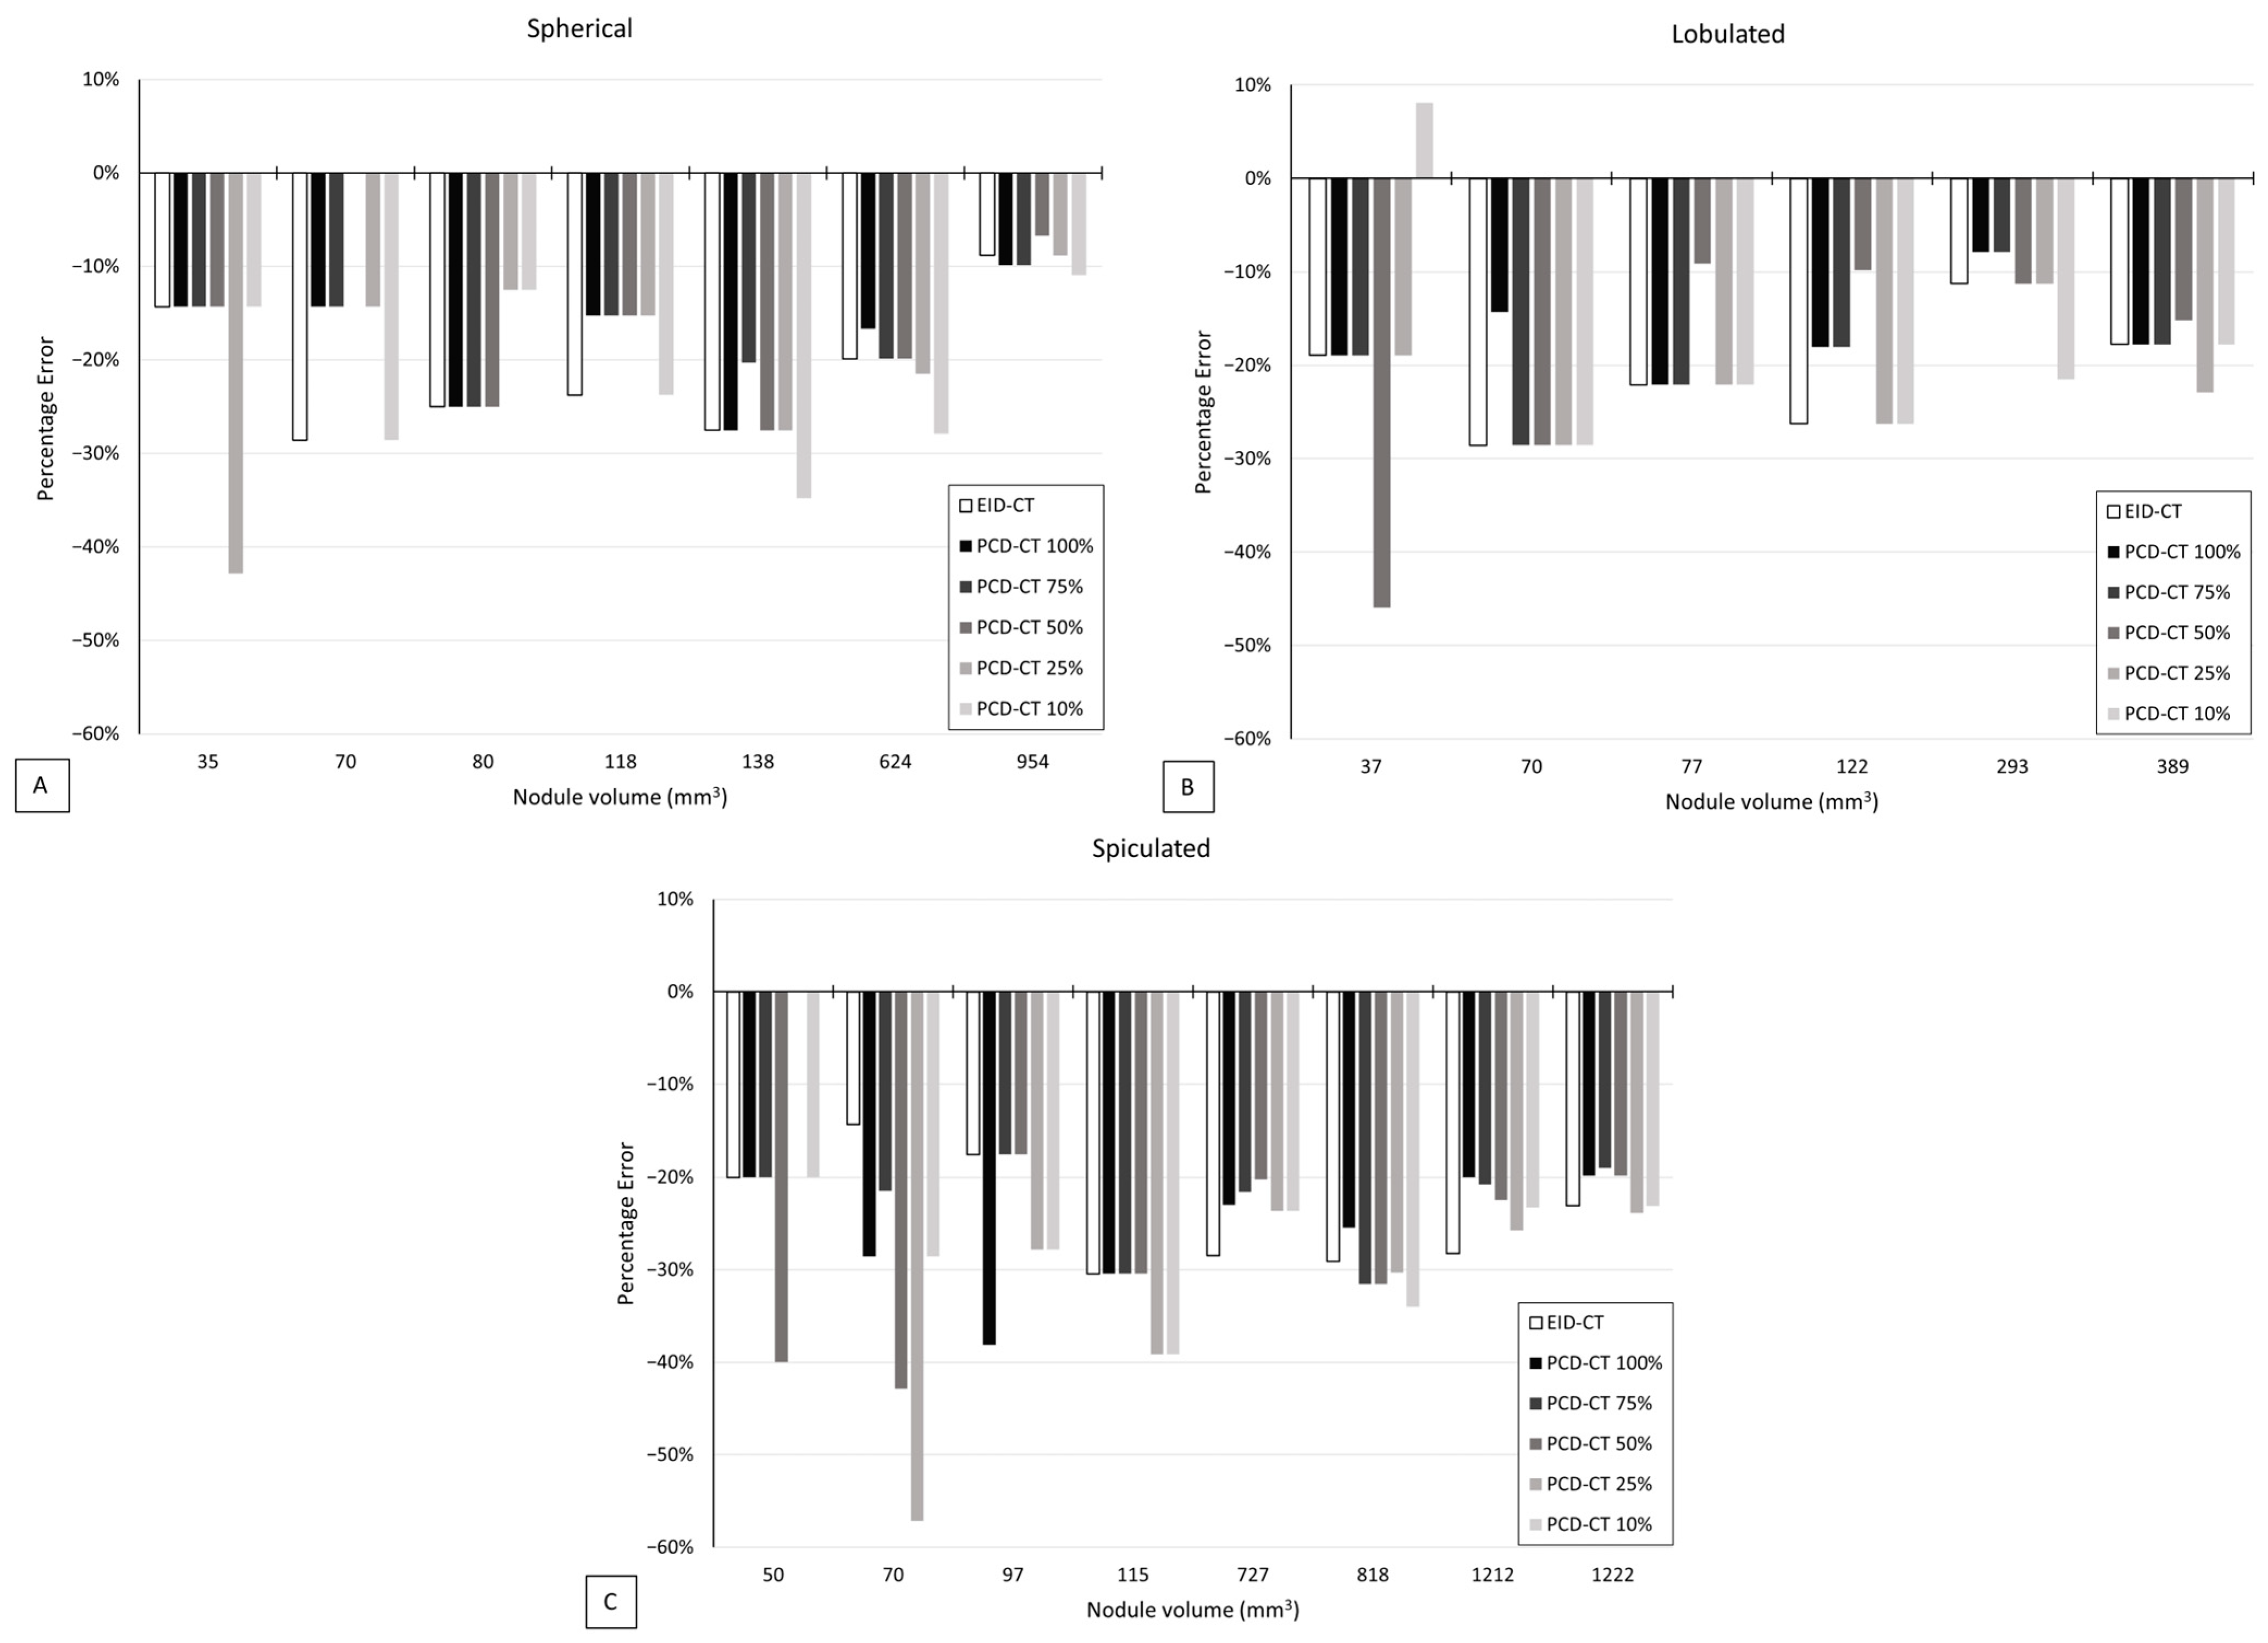

3.2. Volumetric Accuracy